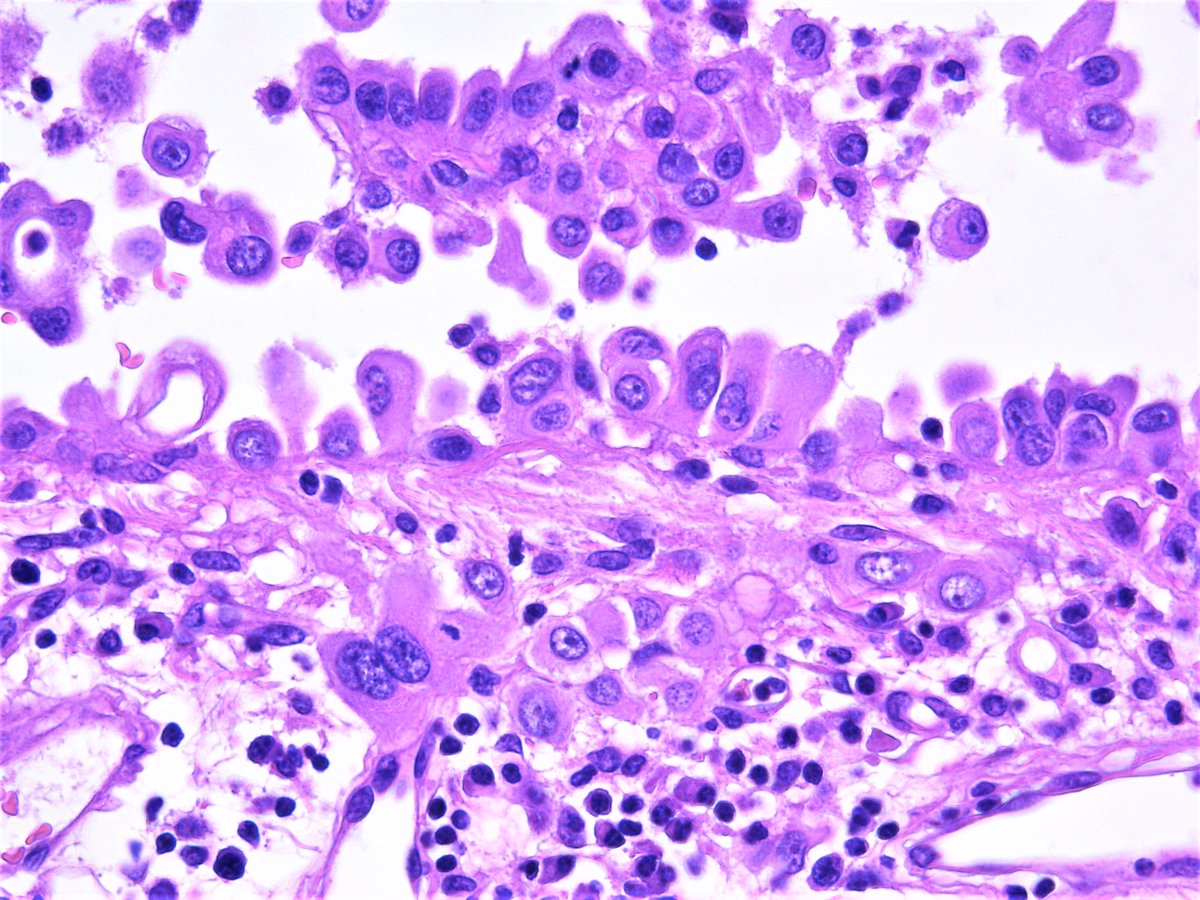

It is more aggressive than epithelioid mesothelioma. epithelioid is the most common mesothelioma cell type. epithelioid mesothelioma cells are square shaped with visible nuclei, and they tend to lump together. It's usually linked to asbestos exposure. It is the most common type of mesothelioma, making up about 70 percent of all mesothelioma cases.

Pure sarcomatoid tumors are uncommon in peritoneal mesothelioma. Papillary is the most common and often appears alongside the others. Please know that there is a distinct way to differentiate cancerous cells from the normal ones. mesothelioma is a type of cancer that develops in the lining that covers the outer surface of some of the body's organs. Specialists have only diagnosed about 30 cases of this variant since 2006. epithelioid mesothelioma is less aggressive than other cell types. epithelioid mesothelioma, also known as epithelial mesothelioma, is the most common form of the disease; Higher magnification shows psammoma bodies closely admixed with neoplastic cells.

It's usually linked to asbestos exposure. epithelioid mesothelioma what is epithelioid mesothelioma? The symptoms are generally the same as patients with epithelioid and sarcomatoid mesothelioma. The who classifications of pleural mesothelioma traditionally recognized the three major subtypes of epithelioid, biphasic, and. Rare types of mesothelioma can also begin in the lining around the heart, called the pericardium, or in the lining around the testicles, called the tunica vaginalis. It is the most common type of mesothelioma, making up about 70 percent of all mesothelioma cases. It is characterized by the presence of cells with epithelioid morphology. In the tubulopapillary growth pattern, it is common to identify psammoma bodies.

It typically has a more positive prognosis compared with sarcomatoid and biphasic tumors. Because they are the most treatable cell type, patients with epithelial cells have the most favorable prognosis. It is not yet understood how histological differentiation of mesothelioma is regulated. Meanwhile, black patients have a higher average survival rate. Figure 1 malignant pleural mesothelioma, epithelioid type. This type of mesothelioma is the most common, accounting for approximately 70% of cases. Forde is a thoracic medical oncologist at sidney kimmel comprehensive cancer center. Malignant mesothelioma is an uncommon form of neoplastic transformation of the mesothelial cells that line the serosal surfaces of the body. Similar but not the same. As is the case with pleural mesothelioma, these tumors often have spread too far to be removed completely. Reactive mesothelial cells also show membranous or cytoplasmic heg1 staining. It is more aggressive than epithelioid mesothelioma. epithelioid mesothelioma what is epithelioid mesothelioma?